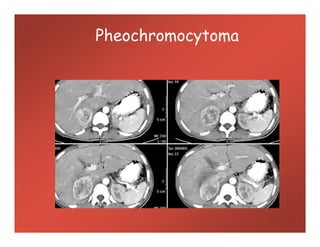

Pheochromocytoma